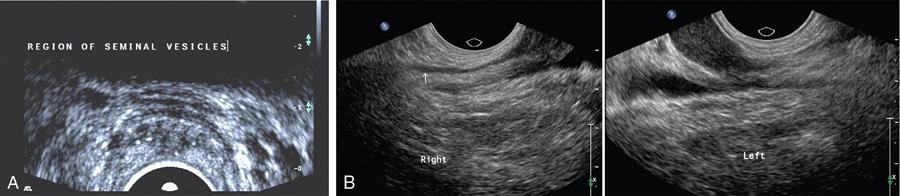

Anidudha Kulkarni Seminal vesicles (SVs) are an integral part of male genitourinary system. SVs are paired accessory gland which plays a major role in male fertility. They produce an alkaline fluid contributing 50%–80% of the ejaculate volume. Male genital organs collectively work to produce semen, consisting of mature spermatozoa. There are no specific signs and symptoms for pathologies in SVs. The common complaints include pain, recurrent UTI and dysuria. Commonly, an abnormality is identifies while investigating for an unrelated pathology such as infertility or a prostatic nodule. SVs are paired organs, measuring 5–7 cm in length, which are rounded superiorly and taper inferiorly. SVs are located posterior to the bladder and inferolateral to the vas deferens. This bilateral positioning of the SVs creates a ‘V’-shaped configuration. SVs are positioned superior to prostate. They lie at the inferior aspect of the rectovesical pouch. SV ducts merge with ampulla of vas deferens and form the ejaculatory duct which opens into the prostatic urethra at the level of verumontanum. SVs contain highly granular cells that produce straw coloured alkaline fluid containing fructose, proteins and vitamin C under the influence of testosterone. The fructose provides the required energy for the motility of spermatozoa. This fluid makes up two-thirds of the total ejaculate volume. Rest of which comes from the prostate gland, vas deferens and lesser amounts from bulbourethral and Cowper’s glands. SVs appear as fluid-filled structures, with a thin septations on contrast-enhanced CT. This modality remains helpful in recognizing many SV abnormalities. On MRI they show low signal intensity on T1-weighted and high signal intensity on T2-weighted images and appear as elongated fluid-filled structures with thin septae. SVs appear as symmetric organs which lie cephalad to the prostate and posterior to the bladder They have a typical ‘bow-tie’ appearance in transverse scans and a club or tennis-racket shape in longitudinal scan. They show homogenously fine echoes, however they are less echogenic than prostate. SV volume is positively affected by circulating testosterone and prolactin, and increases during a prolonged sexual abstinence. Volume of SVs tends to shrink after the fifth decade. SV agenesis is a rare congenital anomaly with an incidence of 0.08%, where there is a complete or partial absence of one or both SVs. This anomaly results in infertility secondary to azoospermia. Patients are generally asymptomatic. Only symptom is infertility and thin low volume ejaculate. TRUS remains the modality of choice to diagnose patients with SV agenesis. There is no treatment available for the SV agenesis. The ureteric bud develops from the mesonephric duct during the 5th week of intrauterine life. In the 7th week, the testes develop and differentiate the male genital system. SVs develop as a bulbous swelling of distal portion of mesonephric duct during the 12th week of gestation. SVs are retrovesicle to the urogenital sinus. SV agenesis is often associated with abnormal development of other mesonephric/metanephric derivatives, such as the VD, ureter and kidney. Unilateral SV agenesis is due to insult occurring before the 7th week of gestation, when the ureteric bud arises from mesonephric duct. Bilateral SV agenesis is related to CFTR gene mutations (64%–73% of cases). A decreased SV volume is defined as hypoplasia, and mainly refers to congenitally small SV, although an acquired form may be associated with testosterone deficiency or postinfective scarring. The normal SV measures >25 mm in length. They are considered to be hypoplastic when >16 mm but <25 mm and atrophic when <16 mm Another parameter which can be considered for hypoplasia is the maximum anteroposterior diameter being smaller than 50% of normal or <5 mm. Hypoplasia of the SVs may be unilateral or bilateral. This condition usually is associated with other genitourinary anomalies such as absence of the ipsilateral vas deferens and ejaculatory ducts.